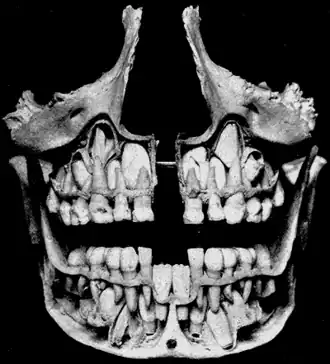

Cross-section of upper and lower jaws with permanent teeth located above and below the deciduous teeth prior to their exfoliation. The deciduous mandibular central incisors have already been exfoliated. | |